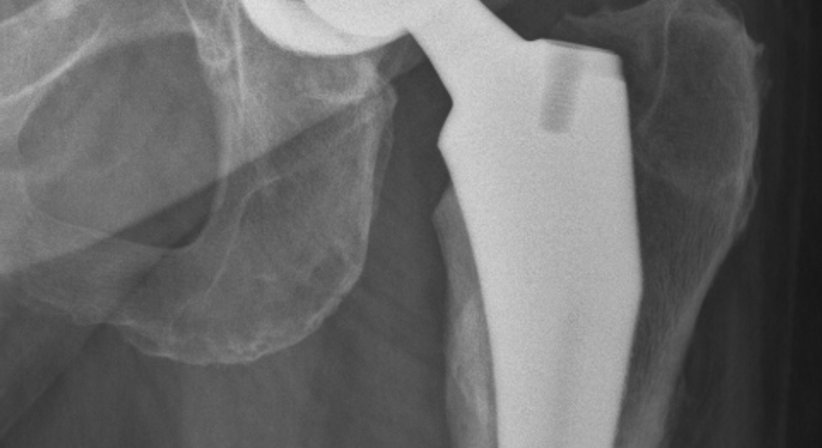

Eine Hüftprothese ersetzt ein geschädigtes Hüftgelenk. Neben Knieprothesen zählen Hüftprothesen zu den am häufigsten implantierten Prothesen im Bereich der orthopädischen Chirurgie, die häufigste Indikation für den Ersatz des Hüftgelenks ist die fortgeschrittene Hüftarthrose (Coxarthrose).

Nach dem Kniegelenk ist das Hüftgelenk das zweitgrößte Gelenk des menschlichen Körpers. Das Gelenk bildet den beweglichen Übergang zwischen dem Becken und dem Oberschenkelknochen. Schmerzen und Bewegungseinschränkungen im Bereich der Hüfte können auf verschiedene Ursachen zurückzuführen sein; ist das Hüftgelenk durch degenerative Veränderungen, Verletzungen oder Erkrankungen stark geschädigt bzw. verschlissen und helfen konservative und gelenkerhaltende Behandlungen (z.B. Physiotherapie, schmerz- und entzündungshemmende Medikamente) nicht mehr ausreichend, um die Schmerzen zu mildern und die Beweglichkeit und Funktionalität des Hüftgelenks in ausreichendem Maß wiederherzustellen, dann sollte über eine Hüftprothese ("künstliche Hüfte") nachgedacht werden, mithilfe welcher die Lebensqualität dauerhaft wiederherstellt werden kann.

Es stehen unterschiedliche Prothesen und Operationstechniken zur Verfügung, um das körpereigene Gelenk zu ersetzen. Der Eingriff kann minimal-invasiv oder offen erfolgen. Die minimal-invasive Methode bietet Patienten einige Vorteile, allen voran, dass die Muskulatur seitlich der Hüfte bei der Operation nicht durchtrennt wird. Dadurch werden Vernarbungen und Heilungsschmerzen an diesen für die Fortbewegung wichtigen Muskeln vermieden, was im Regelfall eine kürzere Rehabilitationszeit bedeutet. Patienten sind nach der Operation schneller wieder selbstständig mobil und können alltäglichen und sportlichen Aktivitäten wieder früher nachgehen. Welche Prothese und Operationstechnik im Einzelfall am besten geeignet sind hängt von der Ausgangssituation des Patienten und individuellen Faktoren ab. Sind die Voraussetzungen gegeben, dann führe ich Hüftimplantationen bei Möglichkeit minimal-invasiv durch.